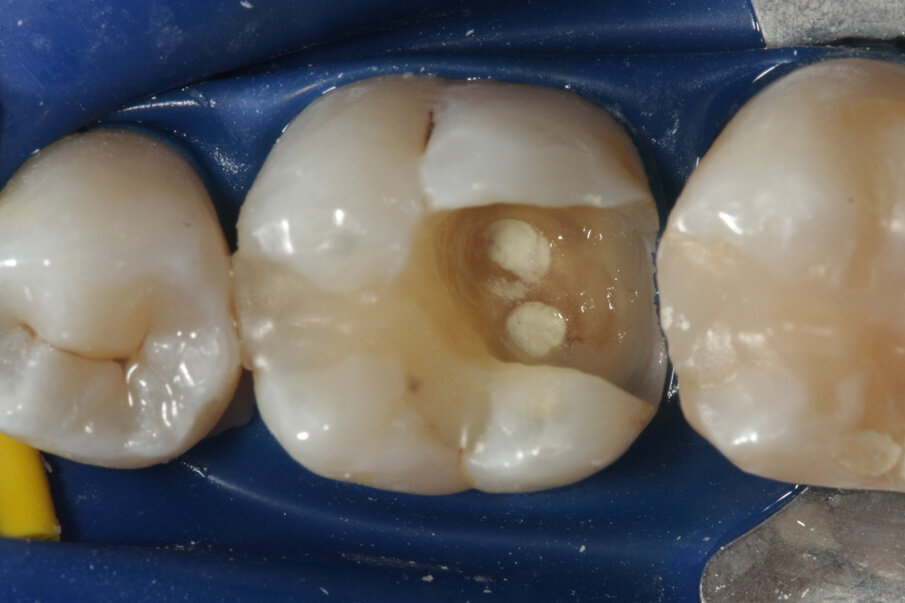

In combinazione con MAP System, Produits Dentaires offre un MTA bianco appositamente sviluppato per il posizionamento con i puntali MAP. Le dimensioni pratiche ottimizzate consentono un’applicazione economica per ogni trattamento. Ci sono molte indicazioni per il PD MTA White, e con il sistema MAP il corretto posizionamento è facile in ogni situazione (Figg. 2a-2g).

Per evitare l’estrusione di materiale da otturazione del canale radicolare in denti immaturi con apici aperti, si utilizza MTA come sigillo apicale. I risultati di molti studi hanno dimostrato che l’MTA induce più spesso la formazione di tessuto duro apicale e che il suo uso è associato ad una minore infiammazione rispetto ad altri materiali di prova (Simon et al. 2007) (Figg. 2a-2g).